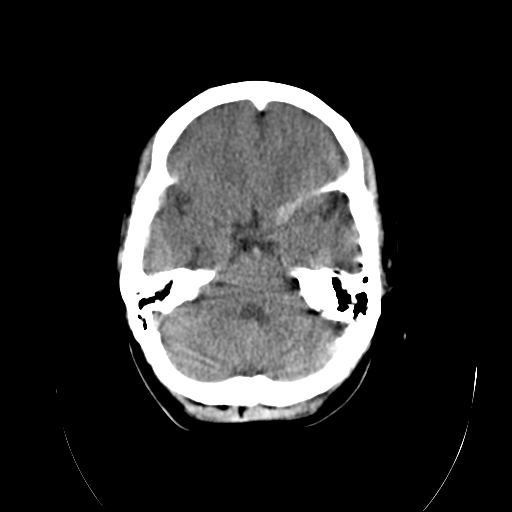

标题: CT18310:女,29岁,头部外伤后头疼、头晕十天。请会诊!! [打印本页]

标题: CT18310:女,29岁,头部外伤后头疼、头晕十天。请会诊!!

外伤性脑肿胀。

脑沟裂池明显变窄,脑室变小。

个人认为诊断外伤性脑肿胀依据不足,首先是临床症状不太支持,第二是影像表现也不支持:年轻人脑室池可这样表现,弥漫性脑肿胀应有水肿导致的实质密度减低从而灰白质分界不清,而本例没有.至于左侧额叶后部裂隙样低密度影,考虑为脑沟,因与外侧脑沟相连.

个人认为诊断外伤性脑肿胀依据不足,首先是临床症状不太支持,第二是影像表现也不支持:年轻人脑室池可这样表现,弥漫性脑肿胀应有水肿导致的实质密度减低从而灰白质分界不清,而本例没有.至于左侧额叶后部裂隙样低密度影,考虑为脑沟,因与外侧脑沟相连.支持!建议短期复查!

先天发育改变,未见外伤性改变

头部ct平扫未见异常